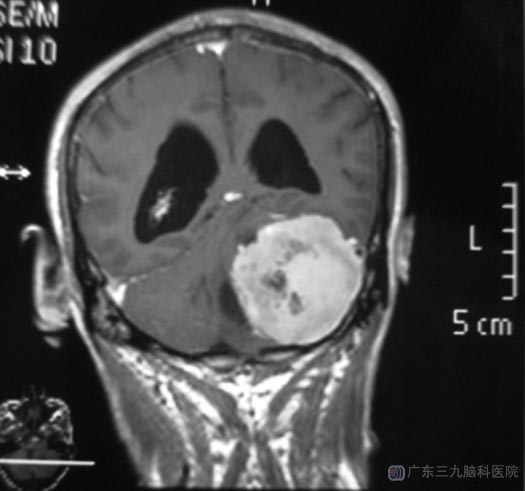

一周前,荣先生感觉走路明显乏力伴不稳,当地医院行头颅CT检查提示:左侧桥小脑角占位、梗阻性脑积水。家人陪着他来到了广东三九脑科医院,头颅MR检查提示:肿瘤大小约47.5mm×58.1mm×60.5mm,脑干及左侧小脑半球受压,小脑扁桃体下疝,初步考虑脑膜瘤。http://www.999brain.com/

▲手术前